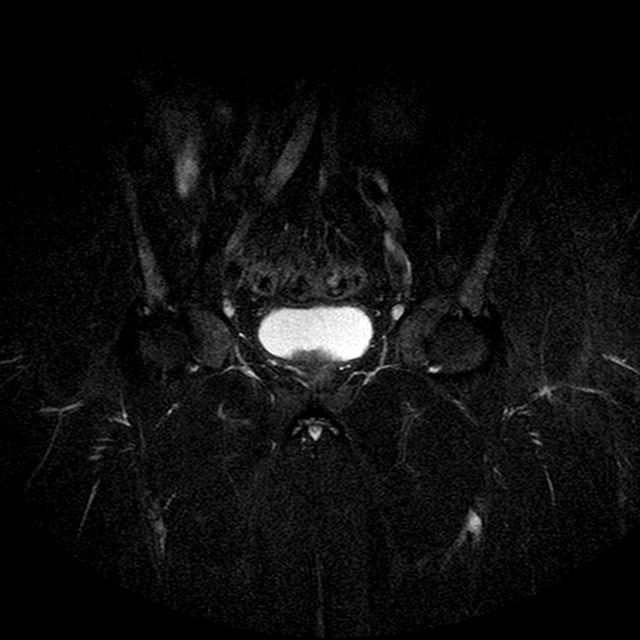

STIR

Evidenti e simmetriche alterazioni osteofitosiche in regione coxo femorale con riduzione delle rime articolari. Degenerazione completa del cercine glenoideo. Non attuali segni di versamento articolare. Non segni di edema osseo che escludono attuale algodistrofia od osteonecrosi. Lieve e simmetrica riduzione del trofismo della muscolatura glutea.